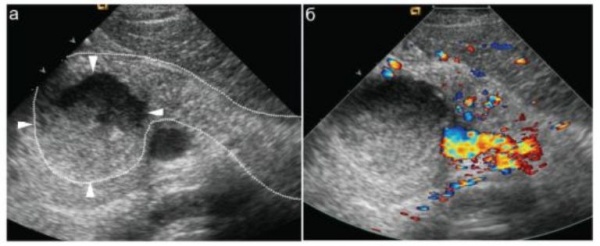

- Визуализирующие методики. УЗИ поджелудочной железы, КТ органов брюшной полости позволит определиться с локализацией и размерами очага, количеством абсцессов. При необходимости возможно одновременное проведение чрескожной пункции с аспирацией, исследованием и посевом содержимого.

УЗИ поджелудочной железы. На фоне резкого увеличения размеров железы (обведена пунктиром) в ее головке определяется крупный (до 3 см в диаметре) абсцесс (показан стрелками).